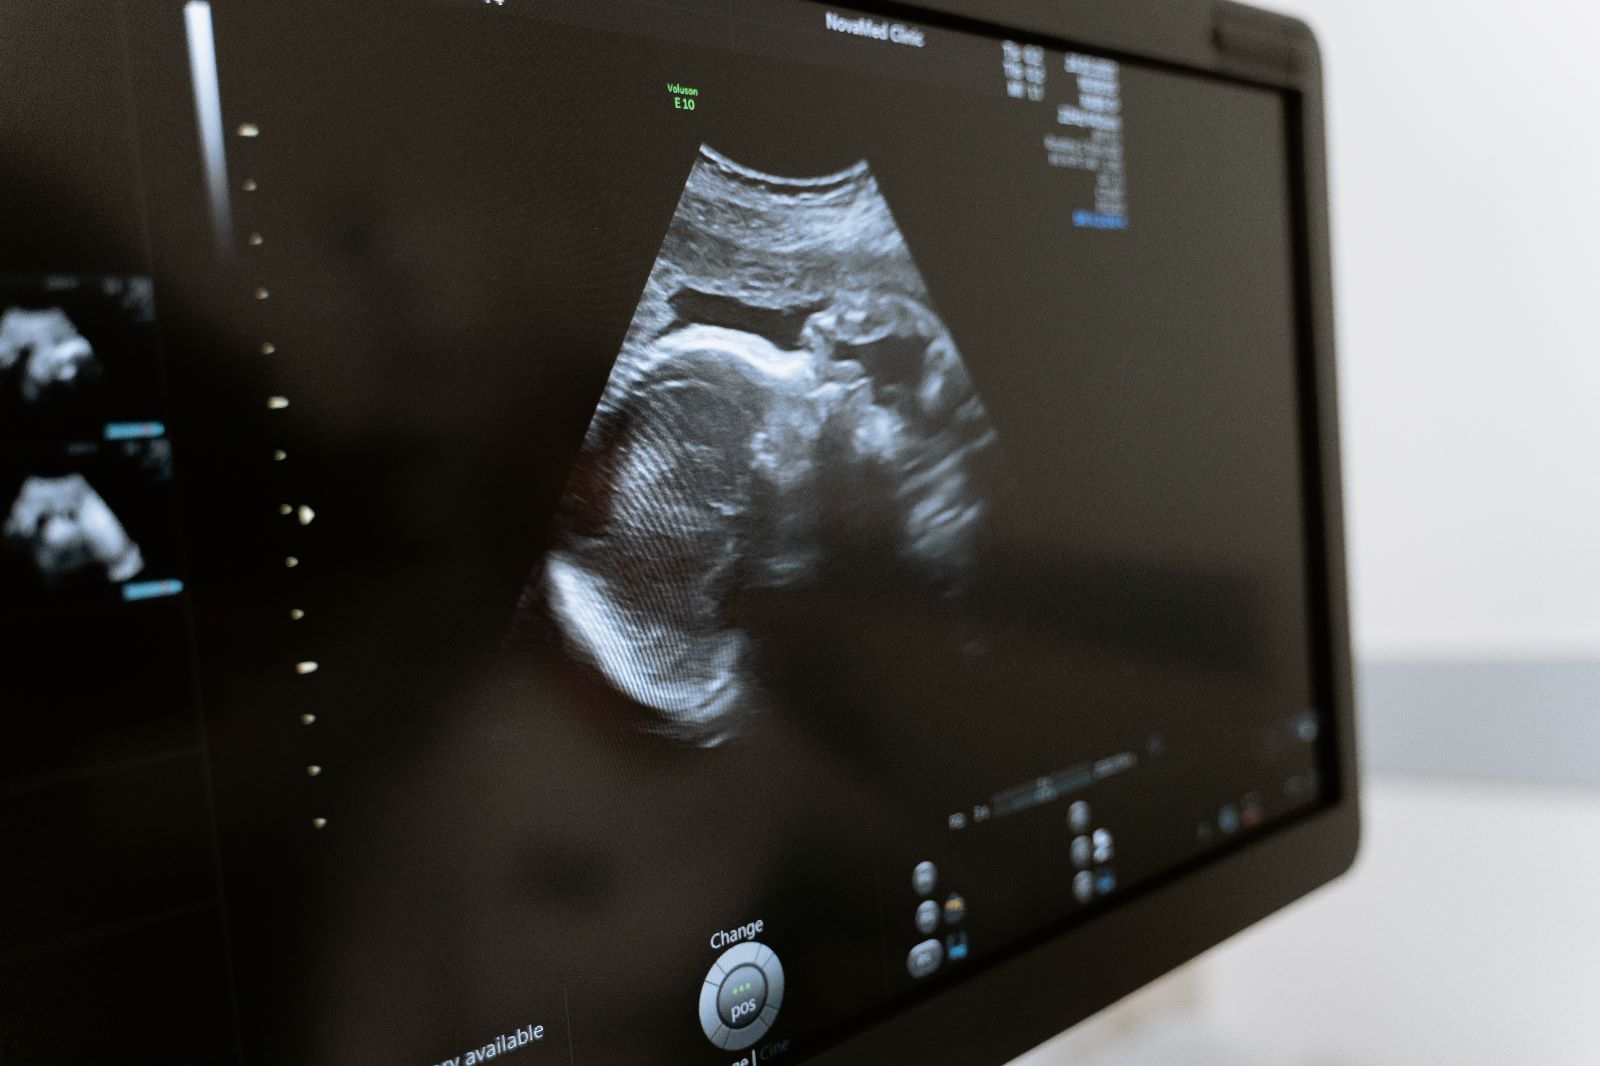

Hamileliğin beşinci haftası birçok anne adayı için hamileliğin ilk keşfedildiği zaman dilimidir. Adet aralıkları uzun olan kadınlarda adet gecikmesi bu haftaya denk gelir ve idrar ya da kan testleri için hazırlıklar başlanır. Hamileliğin bu haftasında yapılan idrar testlerinin doğru sonuç verme ihtimali çok yüksektir ancak hamileliği kesinleştirmek için bir kan testi yapılması gerekir.